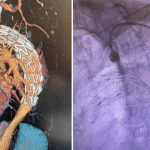

Tevar- in situ fenestracija